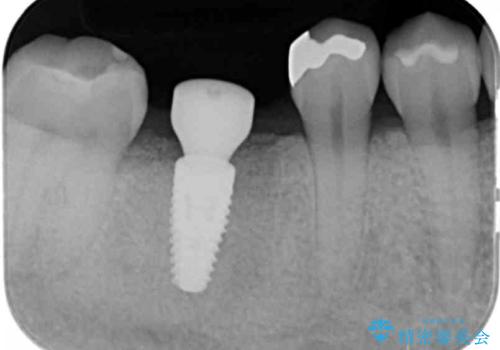

放置した虫歯 インプラントによる機能回復

- 虫歯を数年放置した結果、痛みがひどくなり治療を希望され来院されました。

根だけ残った歯は、破折があり急性の炎症が認められ抜歯が必要な状態です。

抜歯後は、前後の歯を削らずにしっかりと咬合力を回復できるインプラント治療を選択されました。

虫歯の放置により吸収してしまった骨も造成を行うことでインプラント周囲環境をしっかりと整えています。